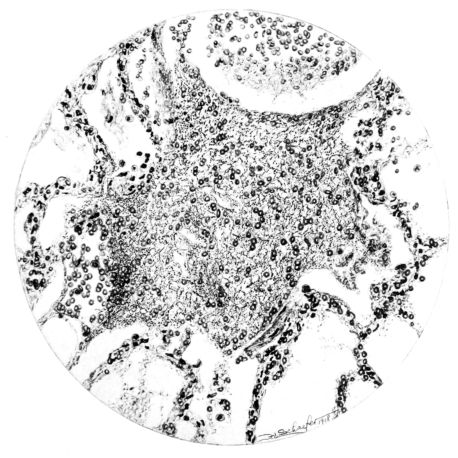

No matter what the portion of the lung from which the sections are derived, the fundamental changes found are the same. The subpleural sheets are spread wide apart, now by empty spaces, now by coagulated fluid. The process extends from the surface through the interlobular septa (Fig. XX), and is accentuated where the connective tissue is more prominent around vessels and bronchi. The nature of the infiltrate in the subpleural and interstitial tissues becomes more evident in the alveoli, which likewise are filled. The material varies somewhat in appearance, probably dependent upon its proteid content. Not infrequently the alveoli contain a homogeneous, pink-staining mass, which resembles the colloid of the thyroid gland. Again, it may be simply a coarse granular precipitate (Fig. XXIII), and in still other instances, small sticks and strands form the bulk of the alveolar content (47, 92, 140, 156). This subpleural, interstitial, perivascular, peribronchial, and alveolar edema, which is a term applicable to this collection of fluid, is very prominent, and although its intensity varies in different portions of the lung; and although it may be replaced in some areas by other types of exudate, unquestionably, this is the dominating expression of the inflammatory process in the early stage of the disease.

As might be expected from the gross appearance, the alveoli vary in size. At times slightly collapsed and at other times overdistended, their lumina are still the seat of the inflammatory exudate, although the mechanical change may allow of some variation in the appearance of their walls. As a rule, however, the alveolar wall is prominent and owes its conspicuousness to the tortuous, engorged vessels within. These vessels contain red blood cells almost exclusively, and on account of the partial, occasionally complete, loss of the lining epithelium, the alveolar wall appears as a huge, dilated arteriole (101) separating the lakes of coagulated material in the spaces (Fig. XXIII). There are areas, as indicated above, where the alveolar content may be more definitely arranged in the form of beaded or homogeneous strands of different caliber; the smallest resemble delicate threads. They tend to converge toward the alveolar wall like wheat in a sheaf, and often pass through this wall by way of the so-called pores of Cohn; as soon as the body of the neighboring alveolus is reached, they again present a fan-like expansion into innumerable, fine strands (Fig. XXII). Where the exudate is more fibrinous, the alveolar wall is less likely to be distended, its vessels are not so prominent, and their content of red blood cells is definitely decreased. Still this is not the most extreme type of alveolar exudate met with at this stage. Perhaps, the most striking, although not the most frequent, exudate has a superficial resemblance to a huge, red blood clot, and it may be difficult to make out the alveolar walls separating the masses of well preserved red blood cells that fill the alveolar spaces. These areas are indistinguishable from infarcts and may be associated with thrombotic arteritis in near-by pulmonary vessels (47) (Figs. XXIV and XXV). Among the red blood cells an occasional strand of fibrin, a desquamated alveolar epithelial cell, and rarely a polymorphonuclear leucocyte may be encountered. The alveolar wall itself varies in the definition of its outline. When its vessels are greatly distended, when its alveolar epithelium is gone, and when its content consists largely of red blood cells, it is difficult to distinguish from the exudate which it encloses. However, when it is more compressed or when its epithelial lining cells are still more or less intact, it may be seen as a blue-staining strand under the low power of the microscope, for the well preserved nuclei lend it prominence.

21There are, of course, variations in the extent of the serum, the fibrin, and the hemorrhage in the exudate of the alveoli, and while these different types may occur as pure forms, often they are associated. In still other areas and varying in prominence, one finds as characteristic an exudate, not only of serum, strands of fibrin, and red blood cells, but also a diffuse dotting of the exudate with bacteria, singly, in pairs, clumps, and chains (92, 164) (Fig. XXI). This type of reaction is uncommon in pulmonary disease. It resembles more closely a streptococcus cellulitis such as is encountered frequently in the subcutaneous tissues, for example, a woody phlegmon, or a sero-hemorrhagic exudate like the avirile response to a rapidly fatal hemolytic streptococcus serositis. A similar reaction has been reproduced experimentally in animals which have been rendered aplastic with benzol previous to pulmonary insufflation, and it is conceivable that the lack of polymorphonuclear response in the inflammatory exudate may be associated with some such general destruction or temporary suspension of leucocytic formation (160).

A more striking picture, however, even than this aplastic alveolar exudate appears in the terminal bronchioles. In many instances, these are conspicuous on account of their size, for they are dilated to form prominent, often irregular, sacs (Fig. XV). The distention of these terminal bronchioles may be so great that the surrounding alveoli are compressed. What makes them even more conspicuous is their lining, once epithelium, but now a swollen, thick, homogeneously staining material, with complete loss of architecture; the material forms (with hematoxylin and eosin) a red band limiting the lung tissue and sharply demarcating it from the exudate within the bronchioles (48, 92). However, this ribbon of red, often thickened by fibrin deposition, is not always pure, for bacteria thrive in the dead tissue. They occur singly, paired, in chains, and also as circumscribed, dense masses which in size and position, simulate nuclei (162) (Fig. XVI). This same hyalinization of the epithelium, it will be recalled, occurs in the larger bronchi (Fig. V), and there, too, bacteria frequently develop in the dead tissue (Fig. VIII). In the smallest bronchiolar ramifications, acute epithelial necrosis is not infrequently encountered, even when the surrounding lung tissue is relatively normal (Fig. XVI). That the process does not stop with the epithelium, but, as in the larger bronchi, may extend through the entire structure of the bronchioles, is manifest. Even the alveolar walls may be involved and frequently homogeneous pink or red bands, now the phantom of the former viable lung tissue, mark the presence of the old wall of the alveolus (Fig. XVII). Occasionally, some architecture remains in this pink ribbon and then the involvement seems to be primarily in the vessels of the wall. Not all the vessels are involved, and next to a hyaline thrombus in one, there may be fresh blood, usually red blood, in its neighbor. The alveolar epithelium is usually denuded and thus accentuates the intensity of the change.